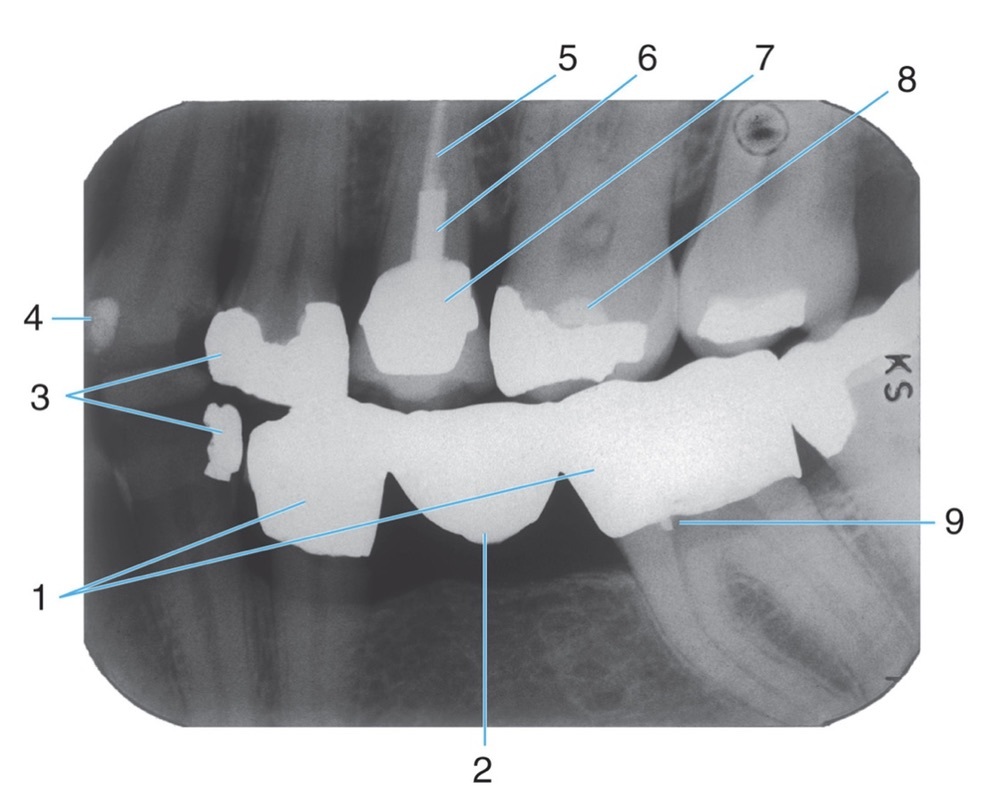

1.

Full metal crowns form bridge abutments

Identify the age of this patient

Age 12

Name the classification of dental caries illustrated by 3

C-3 Advanced Caries

Advanced: Lesion that extends to or through the DEJ but does not extend more than half the distance to the pulp

Identify #5.

Lateral pterygoid

6.

Post and core